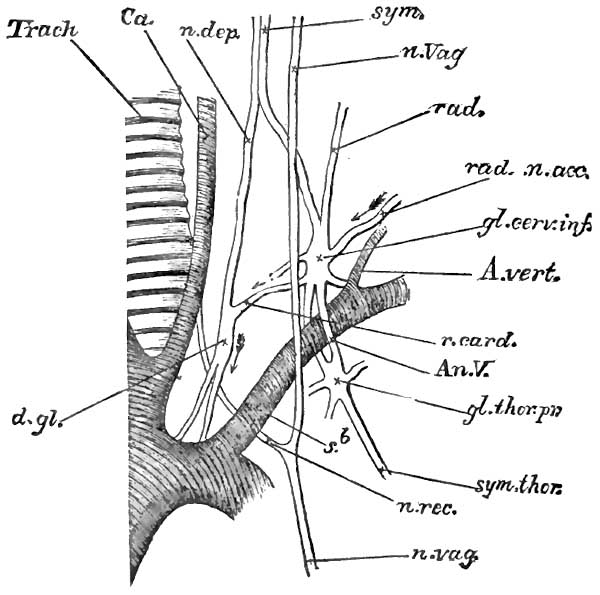

| 2. | THE LAST CERVICAL AND FIRST THORACIC GANGLIA, WITH CIRCLE OF VIEUSSENS, IN THE RABBIT, LEFT SIDE |